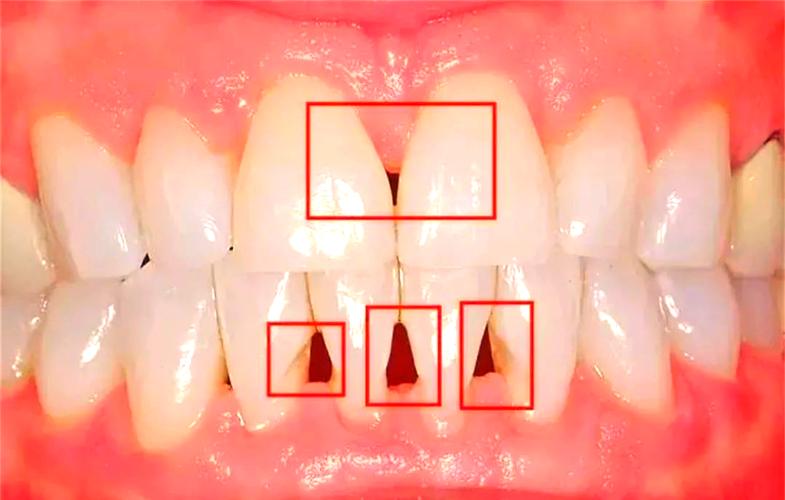

牙齿黑三角是指牙龈萎缩后,牙齿之间出现的黑色三角形间隙,不仅影响美观,还容易藏匿食物残渣、增加蛀牙和牙周炎风险,解决黑三角问题需要根据其成因、严重程度以及个人口腔状况来选择合适的方法,以下是常见的解决方法和思路:

(图片来源网络,侵删)- 年龄增长: 牙龈会随年龄发生生理性退缩。方法: 加强日常维护,定期检查。